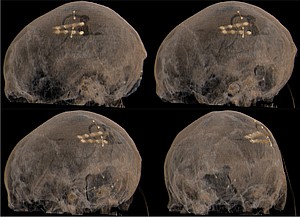

Bei bestimmten Bewegungsstörungen, die nicht oder nicht mehr ausreichend auf eine medikamentöse Therapie ansprechen, ist es möglich, die hierfür verantwortlichen Hirnareale durch die sog. Tiefe Hirnstimulation zu beeinflussen. Hierbei werden feine Elektroden in das Gehirn eingesetzt, um fehlerhafte Nervenstrukturen mit elektrischen Impulsen zu aktivieren oder zu hemmen. Beim Morbus Parkinson, dem essentiellen Tremor oder der Dystonie sind beispielsweise spezifische Hirnareale überaktiv, die dann gezielt durch die Tiefe Hirnstimulation gehemmt und die Symptome wie Zittern oder Muskelsteifigkeit dadurch unterdrückt werden können. Die Hirnregionen selbst bleiben dabei intakt, sodass die Stimulation jederzeit rückgängig gemacht werden kann. Die elektrische Stimulation wird durch einen Impulsgeber gesteuert, der ähnlich wie ein Herzschrittmacher unter die Haut an der Brust der Patient:innen implantiert wird. Die Einstellungen des Impulsgebers lassen sich von außen jederzeit verstellen, sodass die Stimulation an veränderte Bedürfnisse der Patient:innen stets angepasst werden kann.